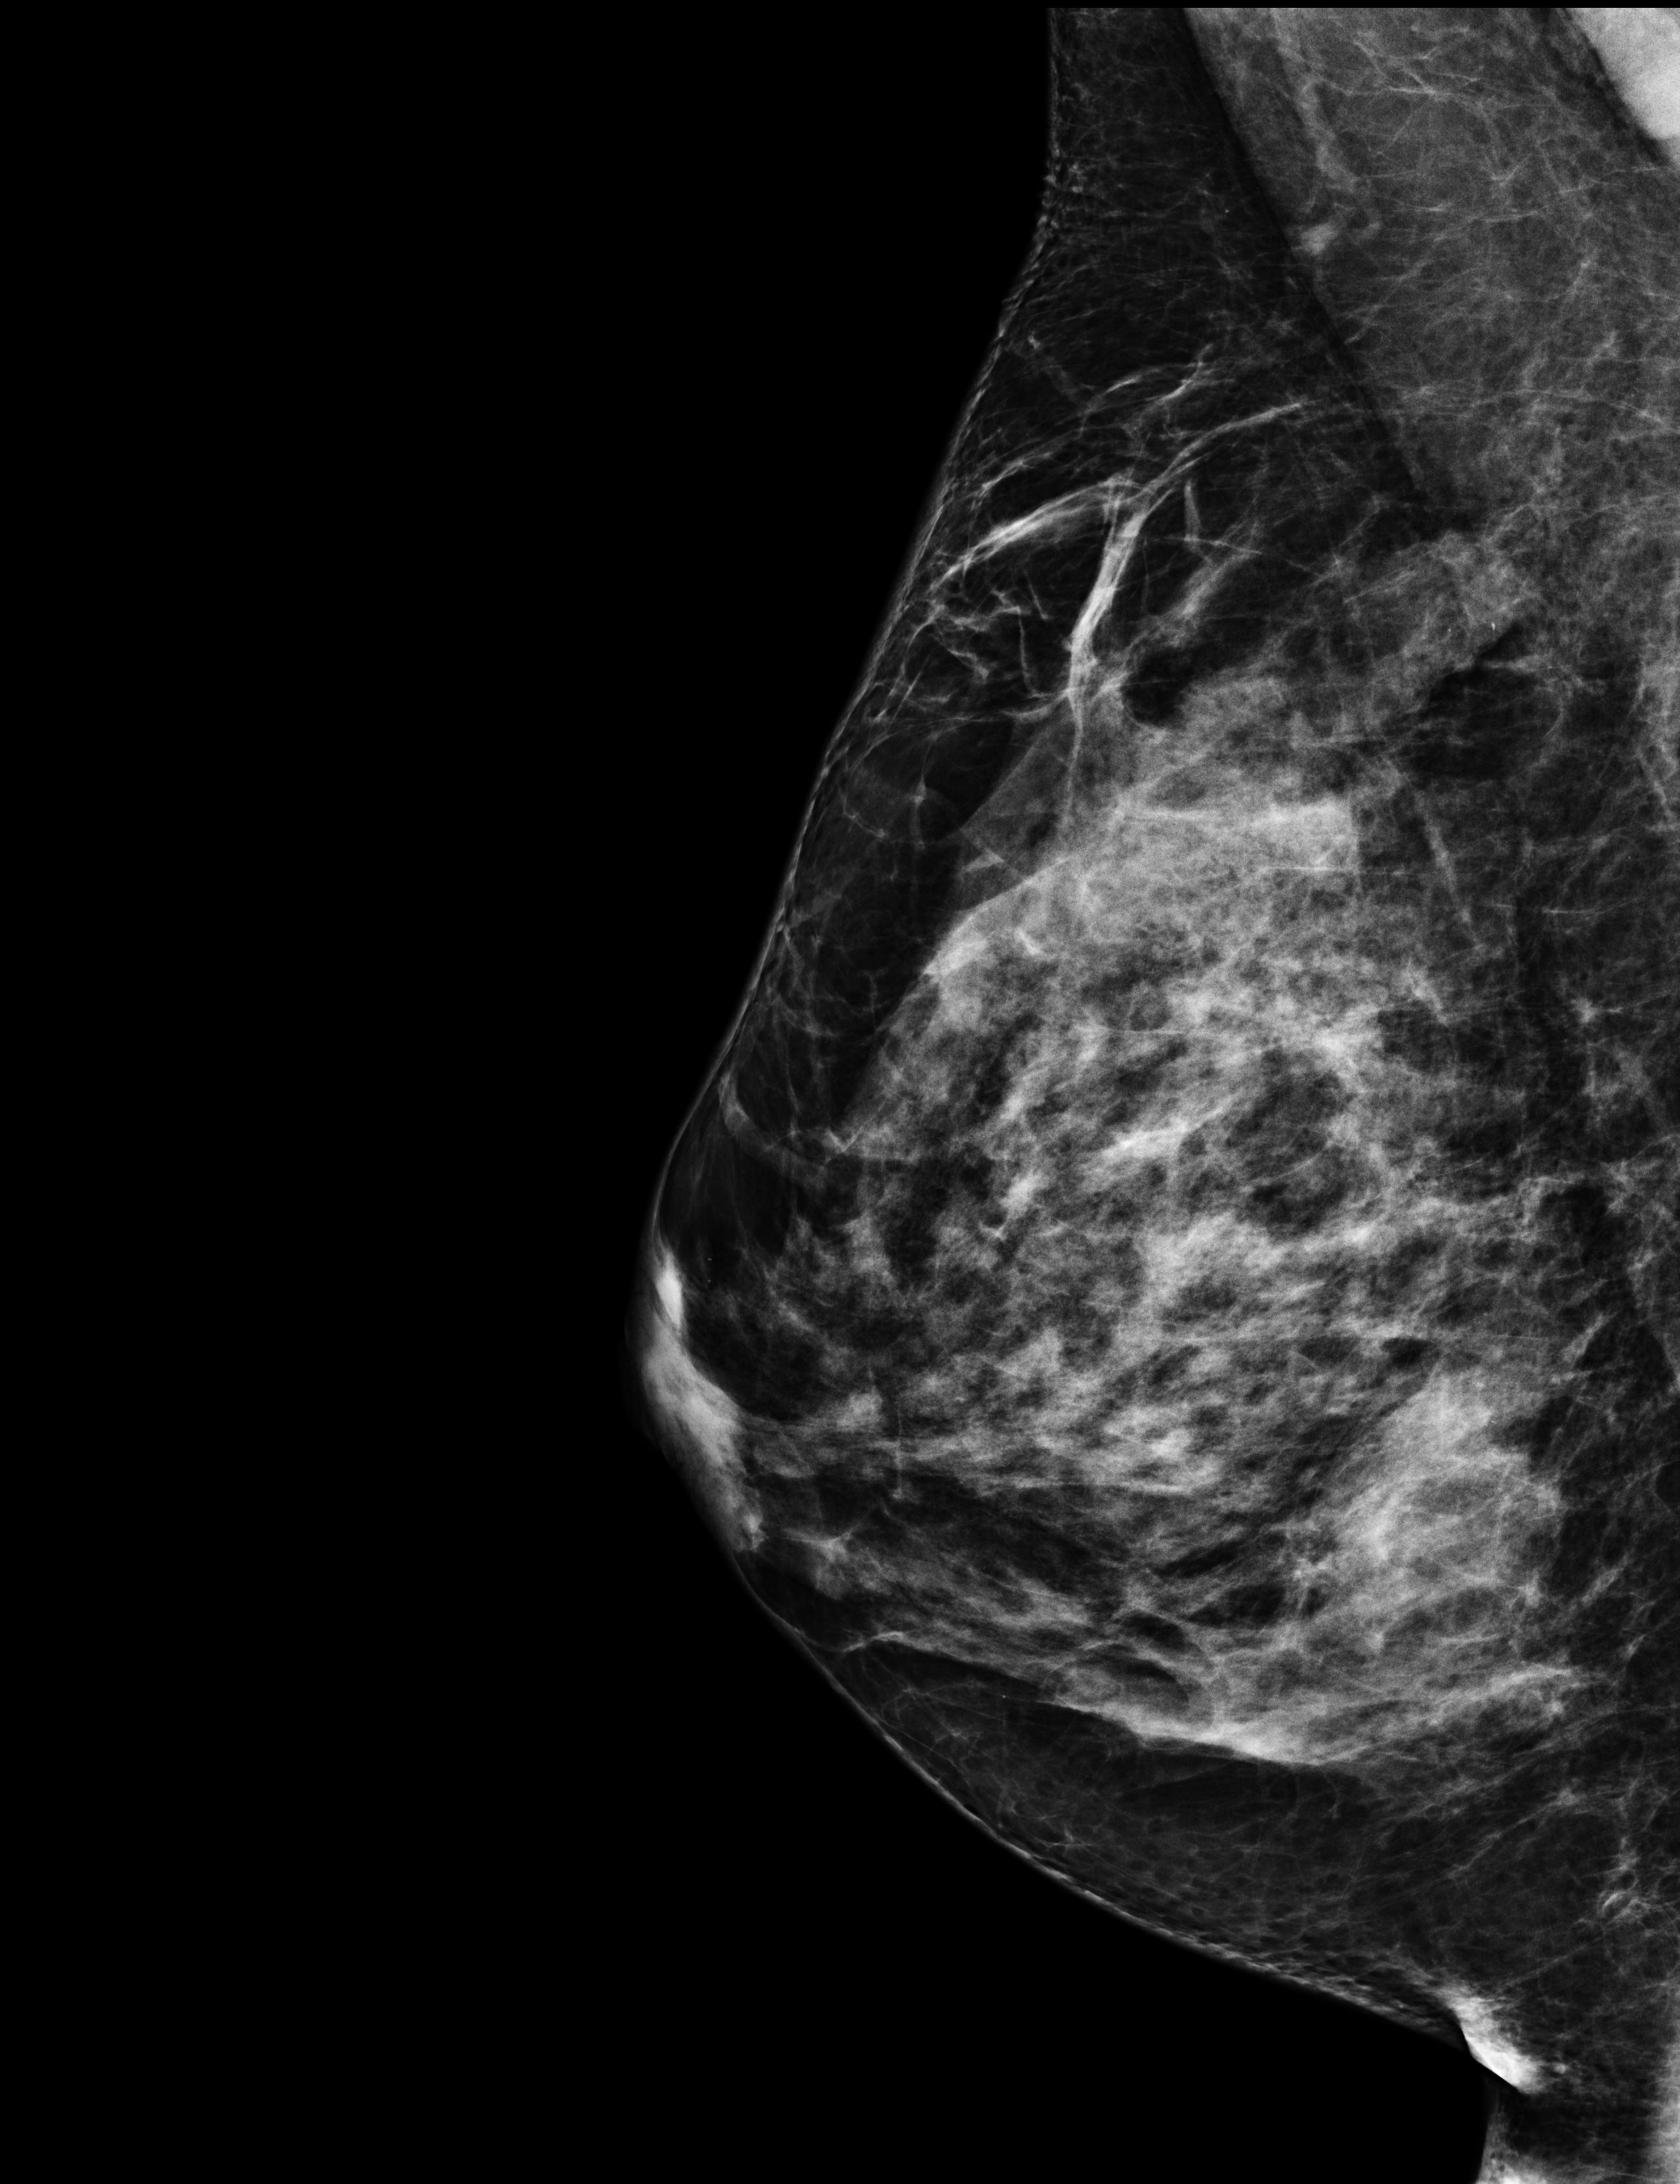

The radiologist that saw me on October 17th, booked me a mammography for 3 days later. I had never done this exam before, and it was very painful, especially because my breast was still suffering from the biopsy. But a mammography can highlight things that an echography cannot, so it was necessary. In the meantime, the results of my biopsy came in, and there was no doubt: “it’s cancer, a breast carcinoma, and unfortunately a triple negative one”, said the doctor.

The data I chose for this event are the four scans of the mammography and a revised version of the biopsy results. The biopsy analysis started on 2023-10-17 at 5:50pm, and it kept being updated until 2023-11-01. I have highlighted in red the medical decisions. At the end you’ll also find a single value, the level of the CA 15-3 tumor marker in my blood. It will come back quite a bit in the following months.